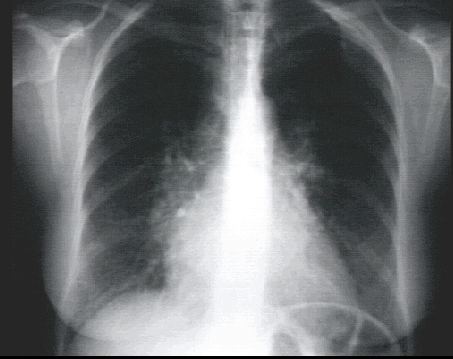

Lateral view

In the lateral view, left atrial enlargement is further reflected by the prominent posterior left atrial shadow. Right ventricular enlargement is best seen in this view and is manifested by obliteration of the retrosternal air space.